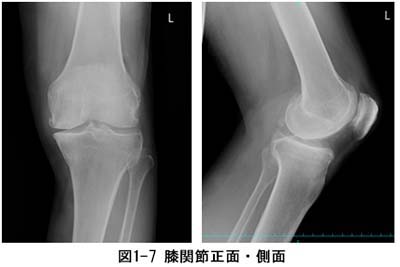

ˆê”ÊŽB‰e‚Æ‚ÍAXüŽB‰eiƒŒƒ“ƒgƒQƒ“ŽB‰ej‚Ì‚±‚Æ‚ÅAŽB‰e•”ˆÊ‚ÉXü‚ƌĂ΂ê‚é•úŽËü‚̈êŽí‚ðÆŽË‚µ‚ÄŽB‰e‚µ‚Ü‚·BŽÊ^‚©‚ç‚ÍA”x‚Ìó‘Ԃ✂̌`ó‚ȂǂðŠÏŽ@‚·‚邱‚Æ‚ª‚Å‚«‚Ü‚·B

“–‰@‚Å‚Í3•”‰®‚ ‚éŽB‰eŽº‚Ì‘S‚Ä‚ÅAƒtƒ‰ƒbƒgƒpƒlƒ‹ƒfƒBƒeƒNƒ^iFPDj‚ƌĂ΂ê‚éÅV‚Ì‘•’u‚𓱓ü‚µ‚Ä‚¢‚Ü‚·i}1-2jB‘S‚Ẳ摜‚ðƒfƒWƒ^ƒ‹‚ň—‚·‚邱‚Ƃɂæ‚èAŒŸ¸ŽžŠÔ‚Ì’Zk‚Æ”í‚΂‚̒ጸ‰»‚ð}‚Á‚Ä‚¢‚Ü‚·B